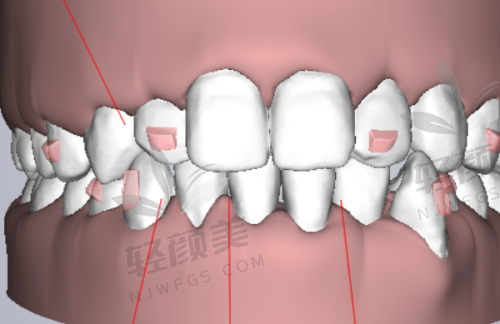

吴忠市利通区洁雅口腔门诊部擅长的项目丰富多样。基础的口腔项目如洗牙、补牙等,门诊部的医生有着娴熟的技术,能够为患者提供优质的服务。洗牙可以有效清除牙齿表面的牙结石、菌斑和色素,预防牙周疾病的发生。补牙则可以及时修复受损的牙齿,修复牙齿的功能和美观。在牙齿矫正方面,门诊部拥有精良的技术和丰富的经验,能够根据患者的牙齿情况和需求,选择合适的矫正方法,如传统金属矫正、隐形矫正等,帮助患者拥有整齐美观的牙齿。种植牙也是门诊部的特色项目之一,医生们具备专精的种植技术,能够为缺失牙患者提供可靠的种植解决方案,修复牙齿的咀嚼功能。此外,门诊部以牙齿美白和牙周病治疗为特色,拥有靠前的牙齿美白技术和专科的牙周病治疗医生,能够为患者解决牙齿颜色和牙周健康方面的问题。

吴忠市利通区洁雅口腔门诊部在技术方面具有诸多特点。首先,门诊部紧跟口腔医学的发展潮流,不断引进精良的治疗技术和方法。在牙齿矫正方面,采用了隐形矫正技术,这种矫正方法具有美观、舒适、可摘戴等优点,受到了特别多患者的青睐。在种植牙领域,运用了数字化种植技术,通过严谨的术前规划和导航,提高了种植的正确性和成功几率。其次,门诊部注重个性化治疗。医生会根据患者的年龄、口腔状况、需求等因素,制定更适合的治疗方案。对于儿童患者,会采用更加温和、舒适的治疗方法,消除他们的恐惧心理。对于老年患者,会考虑到他们的身体状况和口腔特点,提供安心、有效的治疗方案。此外,门诊部还重视医疗质量和安心。在治疗过程中,严格遵守操作规程,确保每一个环节都符合标准。同时,加强对医疗设备的维护和管理,定期进行消毒和检测,确保设备的正常运行和使用安心。